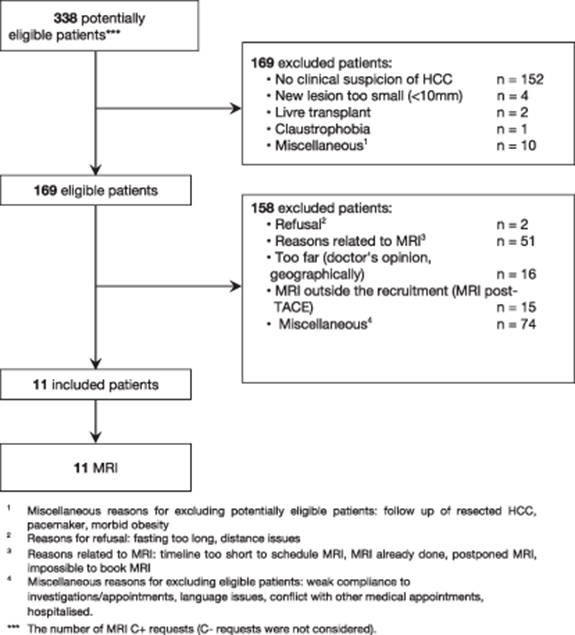

In this pilot study, eleven patients totaling 22 HCCs with tumor diameters between 11 and 52 mm were included. Figure 5 shows the patient selection flowchart and table 3 represents the patients and tumors characteristics. 169 patients diagnosed with HCC and awaiting their clinical MRI between September 2018 and December 2018 were eligible. 11 patients were selected for additional MRI acquisition using the proposed protocol. The most common reasons for excluding patients were related to MRI scheduling (timeline too short to schedule MRI, MRI already done, postponed MRI or impossible to book MRI), distance from the hospital and fasting too long. Thus, a total of 11 patients were included.

Figure 5. Patient selection flowchart.